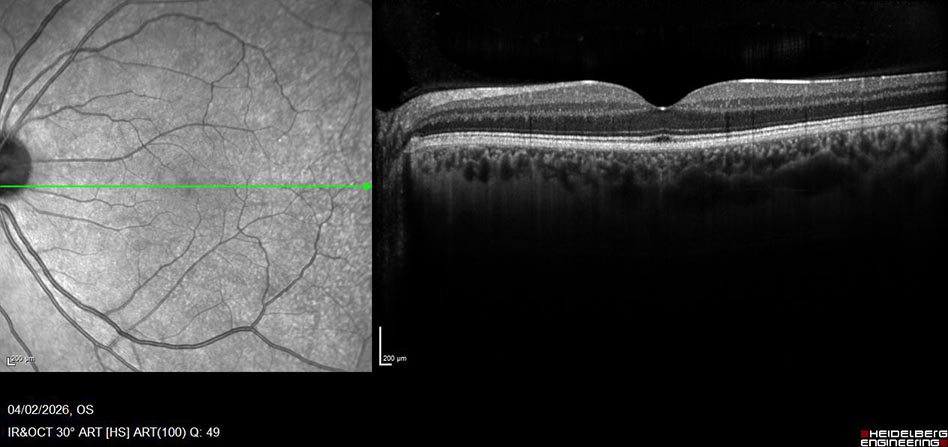

Optical Coherence Tomography, or OCT for short is a scan of the retina at the back of your eye. OCT scans can be taken of both the anterior chamber (front) and posterior chamber (back) of your eye to diagnose and monitor diseases that may affect patients eyes. OCT uses coherent interferometry to construct a cross-sectional view of the ocular structures. Its quick and non invasive with scans being captured in-vivo. Below is an example of a normal OCT scan on patient with no retinal pathology. The scan is focused on the fovea and macula, the fovea responsible for our central vision.

Dry AMD OCT